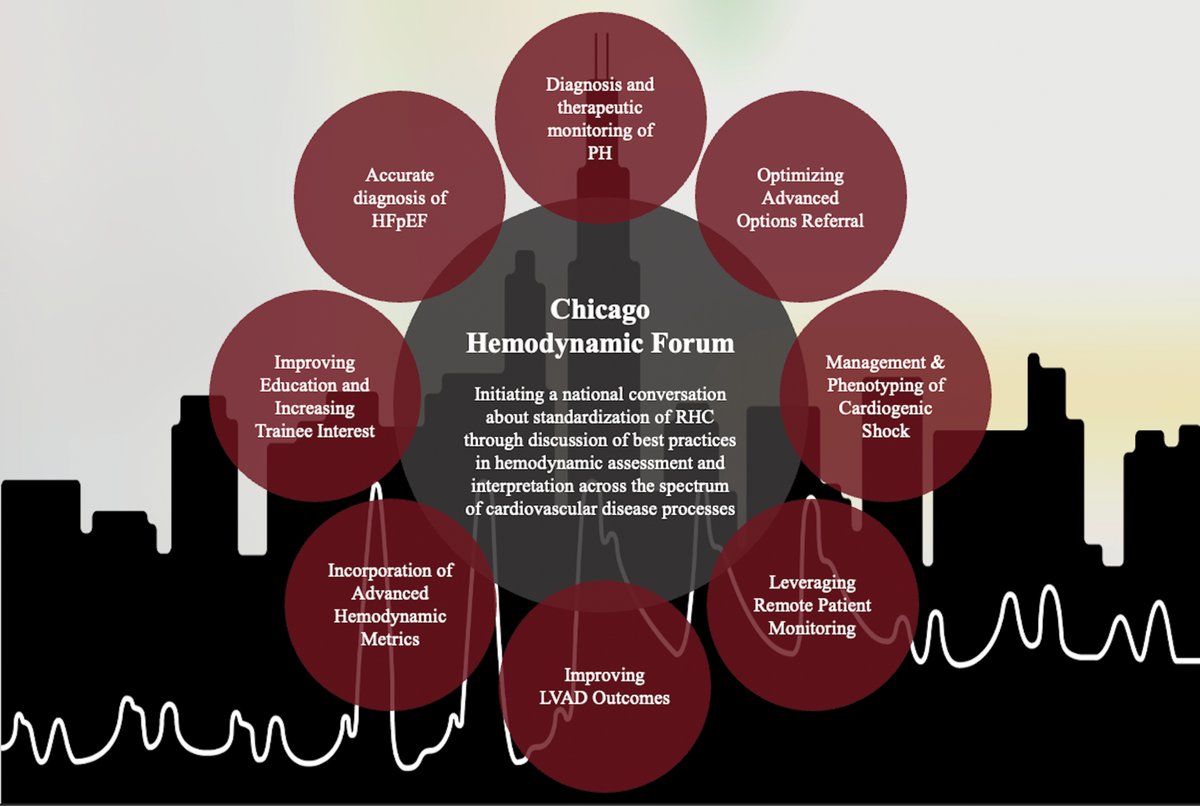

The 1st annual Chicago Hemodynamic Forum was a success! Check out our special report in Circ: Heart Failure reviewing the inaugural meeting ahajournals.org/doi/10.1161/CI… We're busy planning for year 2 - agenda coming shortly Save-the-date: Friday, November 14th in Chicago, IL! Chicago Hemodynamic Forum